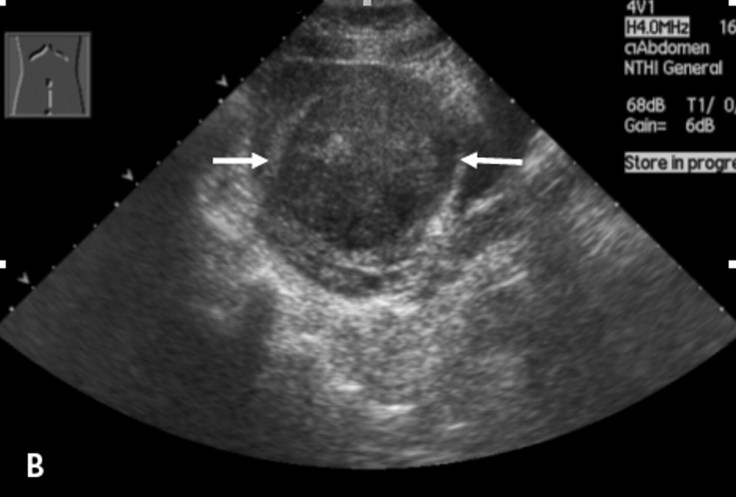

So … anyways … I went to Greg the Gyno yesterday and he said I can no longer have muffler-through-tailpipe surgery because Freddy the Fibroid is now as wide as a full-term baby’s head.

Fortunately, I didn’t have to go pants-less at any stage of the appointment. My ultrasound spoke for itself.